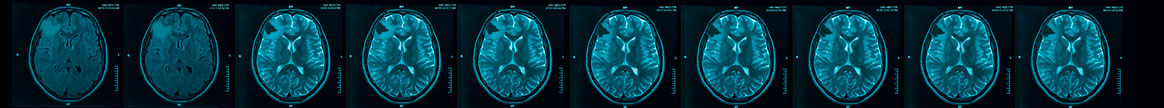

VORANIGO (40 mg tablets) is a prescription medicine used to treat adults and children 12 years of age and older with certain types of brain tumors called astrocytoma or oligodendroglioma with an isocitrate dehydrogenase-1 (IDH1) or isocitrate dehydrogenase-2 (IDH2) mutation, following surgery. Your healthcare provider will perform a test to make sure that VORANIGO is right for you. It is not known if VORANIGO is safe and effective in children under 12 years of age.